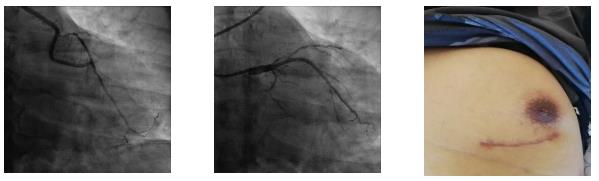

该手术采用“分期式”HCR完成,北京大学人民医院心外科专家陈彧教授首先成功为患者实施小切口搭桥手术,采用左胸前外侧第 4、5 肋间小切口,胸腔镜辅助下完成手术。切口愈合后,包医一附院心内科专家裴汉军团队择期为患者实施了冠状动脉介入治疗,术前冠脉及桥血管造影提示患者内乳动脉桥血流通畅,前降支远端显影良好,吻合口质量极佳,之后成功置入一枚支架。术后患者恢复良好,顺利出院。

裴汉军副院长介绍,这种先搭桥后植入支架的 “分期式”术式是目前应用最为普遍的杂交冠脉血运重建治疗,优势在于可以根据搭桥和介入各自的用药指南进行给药,与“一站式”手术方式比较,出血更少,支架置入后发生术后血栓的风险更低,有桥血管“保驾护航”后置入支架更安全。